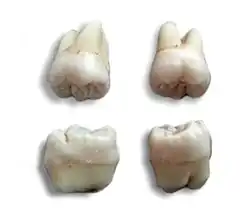

Form und Aussehen

Weisheitszähne weichen häufiger als andere Zähne von ihrer charakteristischen anatomischen Form ab. So treten Weisheitszähne mit drei oder fünf Höckern auf. Auch die Anzahl der Wurzeln ist unterschiedlich. Sie können miteinander verwachsen oder hakenförmig gebogen sein, so dass eine gegebenenfalls notwendige Extraktion der Zähne erschwert ist. In seltenen Fällen wachsen hinter den Weisheitszähnen noch überzählige Weisheitszähne, so genannte Distomolaren, auch Neuner genannt.[2]